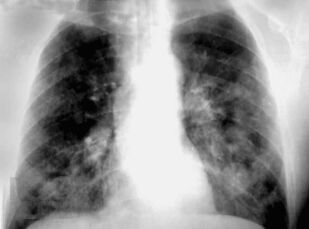

Книга профессора П.В. Власова посвящена современному состоянию лучевой диагностики заболеваний органов грудной полости. Она является первой в отечественной литературе крупной работой, в которой освещена диагностика заболеваний органов грудной полости: острых пневмоний и плеврита, хронических неспецифических заболеваний легких, туберкулеза органов дыхания, рака легкого, опухолей плевры, диффузных и диссеминированных процессов легких, опухолей и кист средостения. Все вопросы рассматриваются с учетом самых современных взглядов на патогенез и диагностику заболеваний.

Большим достоинством книги является комплексный подход к диагностике заболеваний. Наряду с традиционными методами ретгенологического исследования, такими как рентгенография и линейная томография, в книге получили полное освещение роль и место в современном комплексе диагностических средств такие методы, как компьютерная томография и ультрасонография, значительно расширившие возможности диагностики заболеваний.

Второе издание дополнено новым материалом, касающимся пневмоний, синдромов респираторной недостаточности и пневмокониозов, что заметно повысило его информативность и практическую значимость.